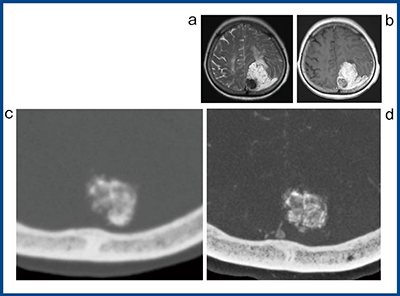

図5は髄膜腫(meningioma)の症例だが,MRIのT2強調画像(a)と造影画像(b)で内部に石灰化を伴う高信号の腫瘤が認められる。ADCT(c)とAquilion Precision(d)で撮影した画像で石灰化の部分を拡大すると,Aquilion Precisionでは石灰化の内部は必ずしも均一ではなく,部分的に高濃度な部分とラフな部分が混在した状態であることが観察できる。脳腫瘍の診断ではMRIが主に用いられることが多く,CTによる評価はおろそかになりがちだが,Aquilion Precisionの超高精細画像はADCTではわからなかった新たな情報が描出できる。脳腫瘍にもいろいろな種類があるように,石灰化も腫瘍によってさまざまなパターンがあることも考えられる。超高精細CTがもたらす新たな知見を生かした読影が求められる。

図5 髄膜腫(meningioma)の比較画像

a:T2強調画像 b:造影MRI c:ADCT d:Aquilion Precision